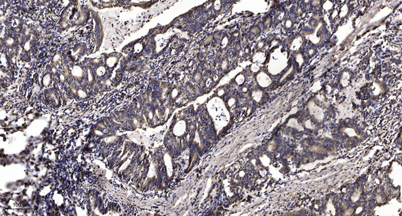

Met (Phospho Tyr1235) rabbit pAb

IHC

IHC-p 1:50-300